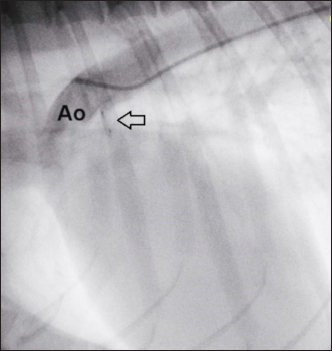

Anesthesia was induced and maintained as previously described (Bagardi et al., 2022) and perioperative intravenous amoxicillin (22 mg/kg) was administered. The dog was placed in right lateral recumbency on a fluoroscopy table (C-arm: Siemens Cios Select Siemens Healthcare), and the area over the right femoral artery was clipped and prepared for surgery. The patient was monitored with transesophageal echocardiography (TEE; Probe: 5VT, Siemens Healthcare), which allowed optimal visualization of the ductus and its measurements (MDD 1.2 mm, ampulla diameter 3.8 mm, and length 4.4 mm), which confirmed the choice of the device (Fig. 3).

Fig. 3. Intraoperative TEE showing PDA and its measurements (MDD: 1.2 mm; ampulla diameter: 3.8 mm; length: 4.4 mm) and the flow from the aorta to the pulmonary artery (MPA) on CFM Doppler (Dual-mode).